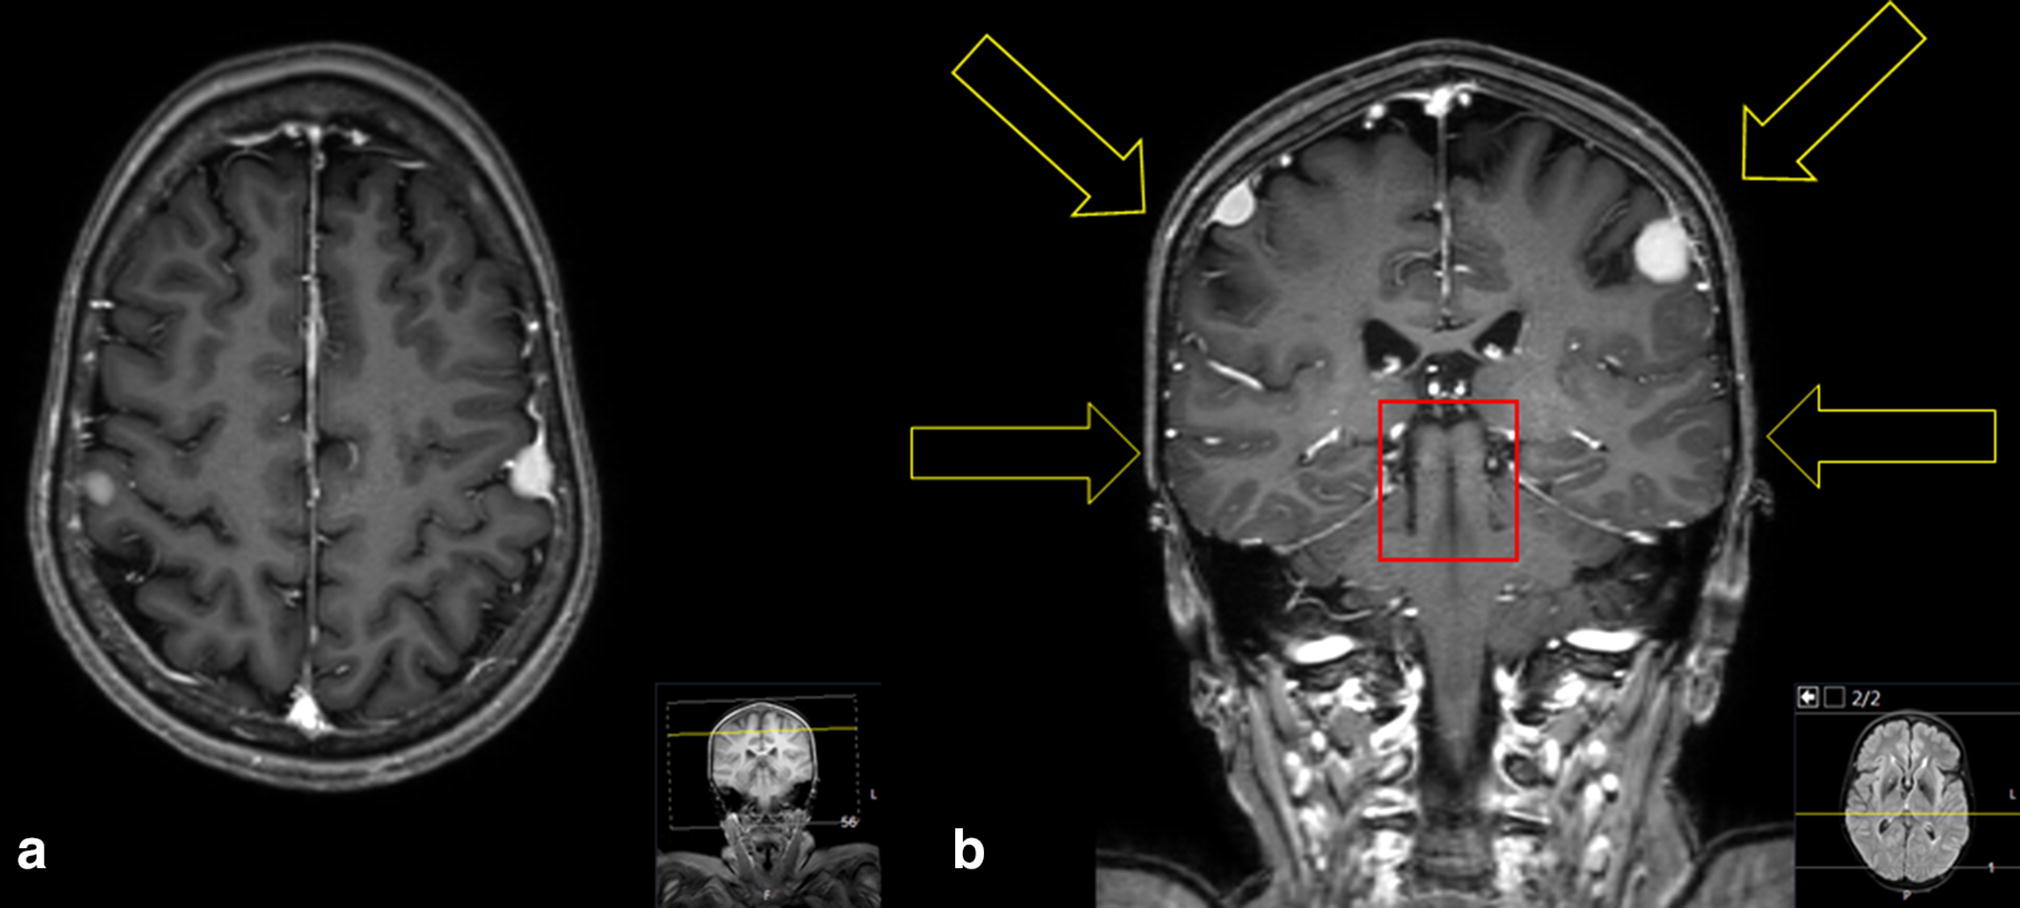

A 40-year-old woman without any known genetic predisposing disease presented to the outpatient consultation clinic with complaints of memory loss without any daily living limitations. Her past medical history was remarkable for central nervous system conventional radiotherapy treatment at a dosage of 50 Gy for craniopharyngioma 35 years before (at the age of five). She was also receiving levetiracetam for symptomatic epilepsy which was well controlled. At examination, she scored 25 out of 30 on the Montreal Cognitive Assessment test, presented slight microcrania and moderate alopecia. The rest of the neurological examination was unremarkable. The brain magnetic resonance imaging revealed the presence of avidly contrast enhancing mirror convexity meningiomas located near the supramarginal gyrus (Fig. 1a). Previous specific and detailed radiotherapy plan of the patient was not available, but the lesions have developed along the radiation trajectory (Fig. 1b). Contrary to radiation-induced meningioma which are a frequent and well-described complication of radiotherapy [1, 2], the occurrence of mirror meningioma is seldom reported [3, 4]. Other locations of mirror meningiomas reported in the literature are the sphenoid bone, optic nerves, parasagittal, falx or foramen magnum [4]. The causal association between the childhood radiotherapy and the late occurrence of the meningiomas here described is reinforced by the coherence of the tumor location and the entrance fields of the radiotherapy treatment for craniopharyngioma.

T1-weighted axial (a) and coronal (b) brain magnetic resonance imaging showing mirror convexity meningiomas located near the supramarginal gyrus. Main radiation entry zones (yellow arrows) and the close tumor area (red rectangle) are represented (b)